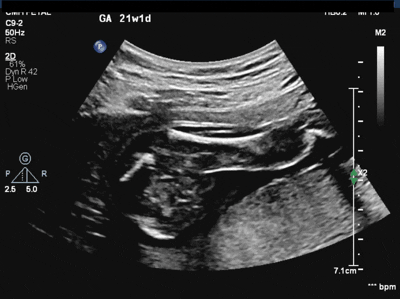

What congenital defect is shown here?

What is Absent Pulmonary Valve